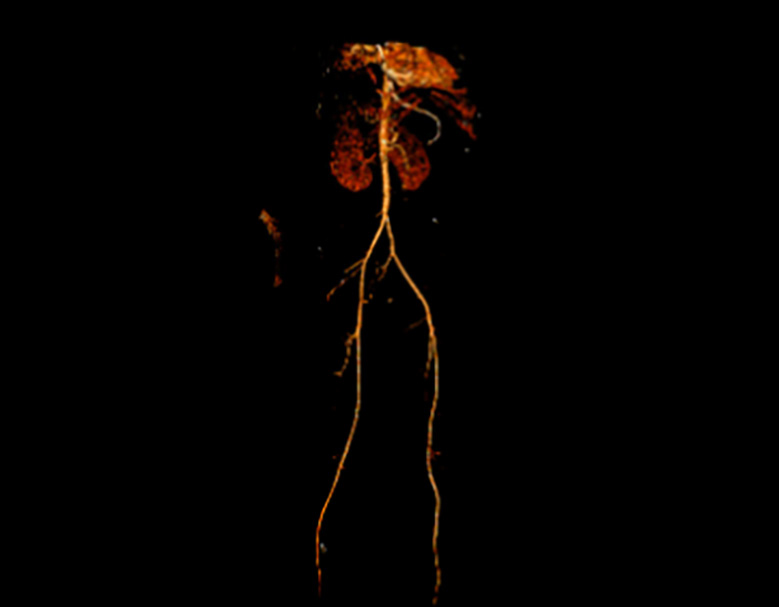

Despite initial control, the patient experienced recurrent hematemesis with his hemoglobin decreasing from 13.4 g/dL to 8.0 g/dL. Epinephrine was administered locally, but no active bleeding was identified. With worsening hemodynamic instability, interventional radiology was consulted, and a CT with angiography was performed. The angiogram showed no active GI bleed but did reveal a large intragastric blood clot (12 cm). The patient was transferred to the ICU after a 30-hour bleeding-free interval, and interventional radiology performed an empiric embolization of the gastroduodenal artery using 500–700-micron particles. However, this failed to achieve adequate control of the bleeding (Figure 2).

Figure 3

Figure 3. A CT Aortogram with bilateral lower extremity runoff via the posterior tibial artery shows no evidence of thrombus or embolus.